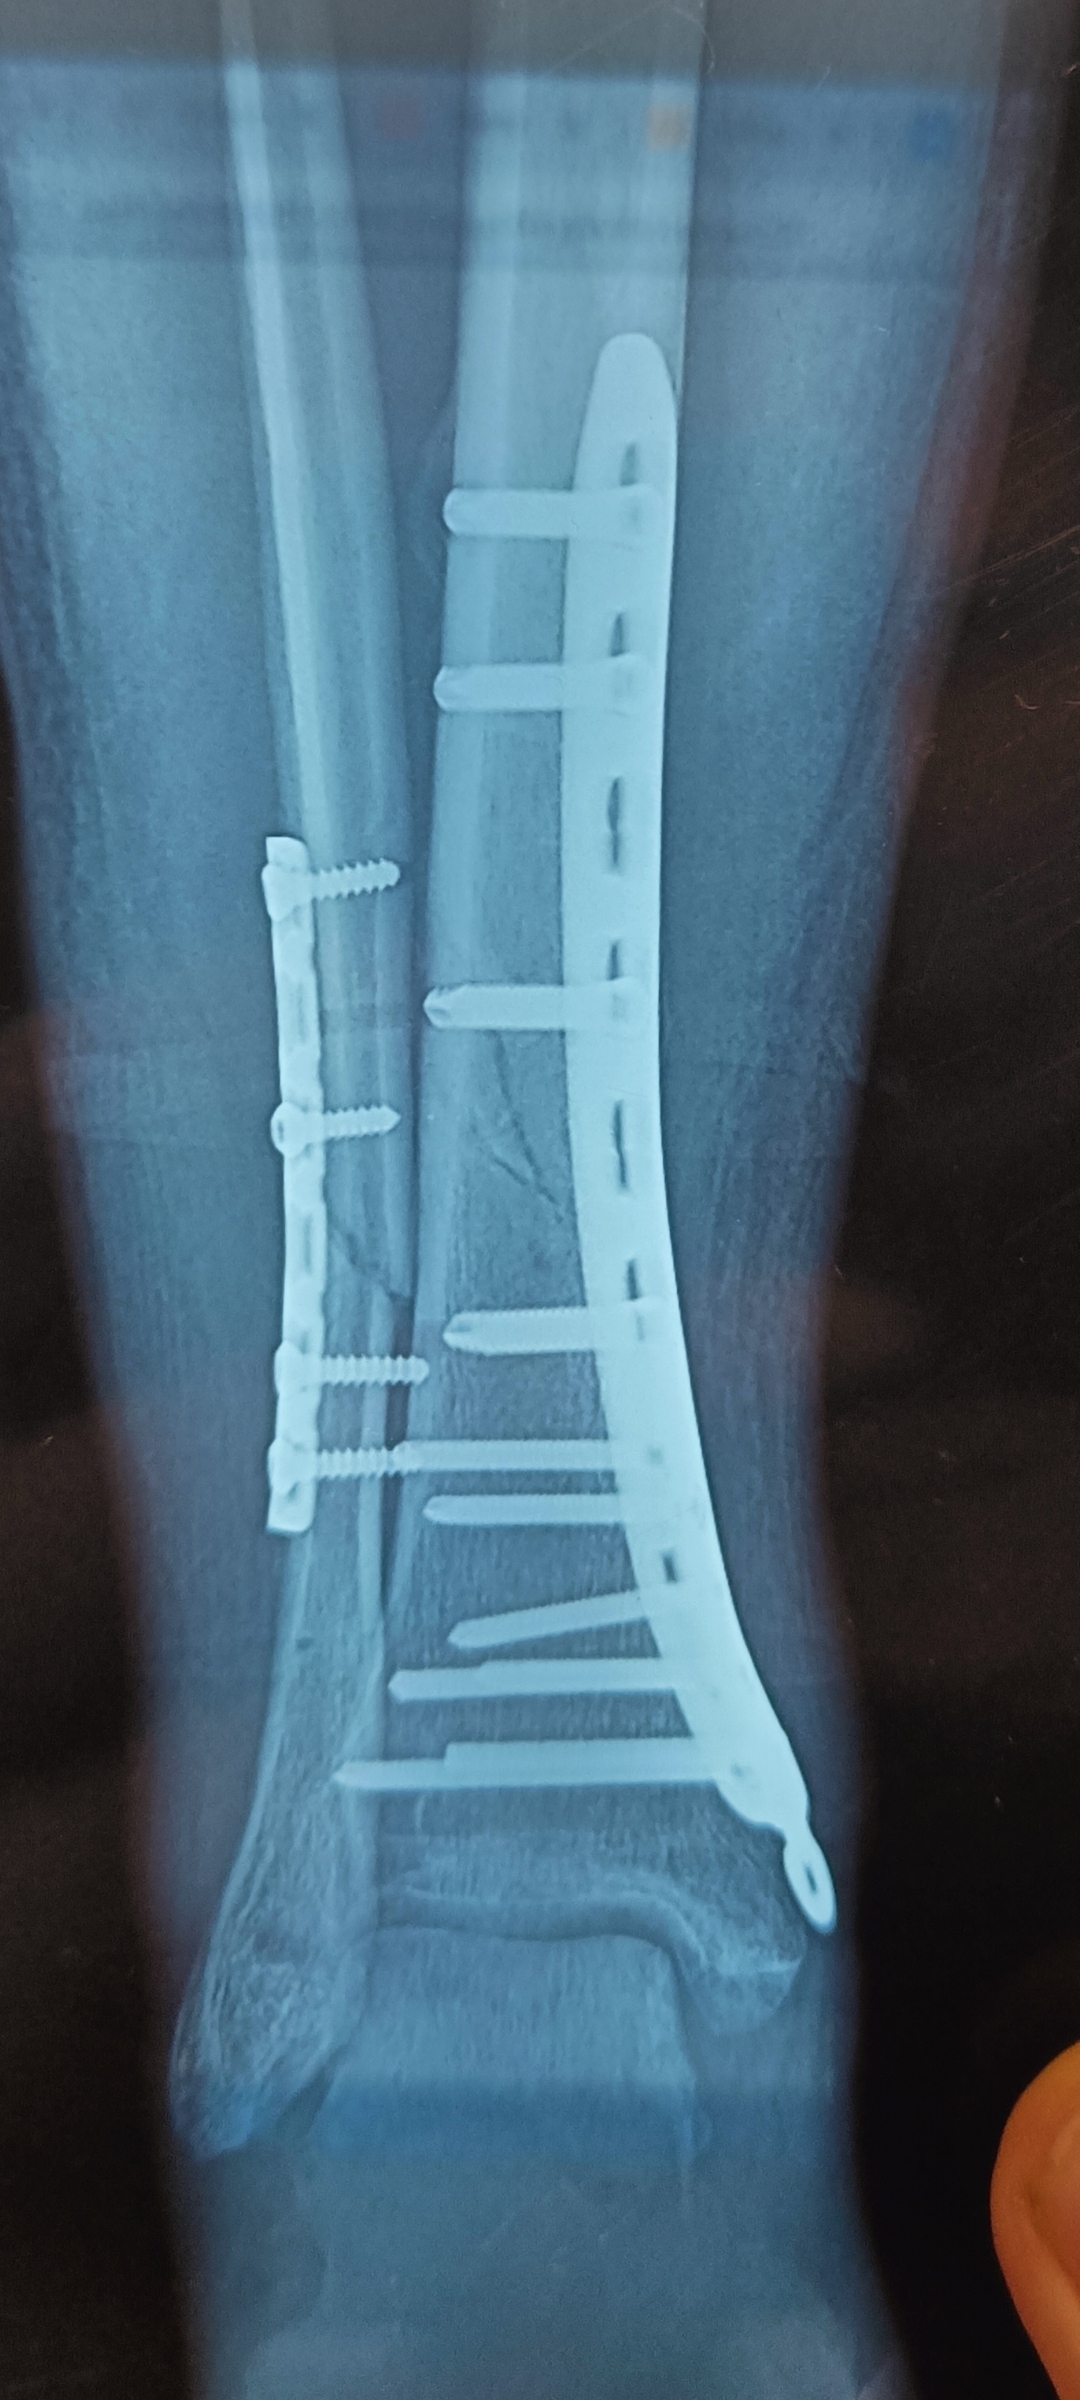

Остеоси́нтез - хирургическая репозиция костных отломков при помощи различных фиксирующих конструкций, обеспечивающих длительное устранение их подвижности. Цель остеосинтеза — обеспечение стабильной фиксации отломков в правильном положении с сохранением функциональной оси сегмента, стабилизация зоны перелома до полного сращения.

Операция была ночью, укол в шею был достаточно болезненный но минут через 5 после него у меня перестала болеть рука от слова совсем. Убедившись в том что рука онемела, врачи начали резать мою плоть. Прикосновения скальпеля к коже я прекрасно чувствовал но это не было больно. Без длительно ожидания мне начали в катетер добавлять пропофол после чего картинка в глазах поплыла и единственное что я помню - врач анестезиолог сказала "заказывай сон". Очнулся я под конец операции но отчётливо помню звук работы "шуруповёрта" при помощи которого мне крепили пластину к кости но я к этому так спокойно относился, по всей видимости из-за пропофола который мне дали что бы спал. Самым больным и неприятным в операции для меня было - зашивка нитками, почему то анестезия тут не работала и пришлось терпеть, благо процедура заняла по ощущениям не более 5 минут.